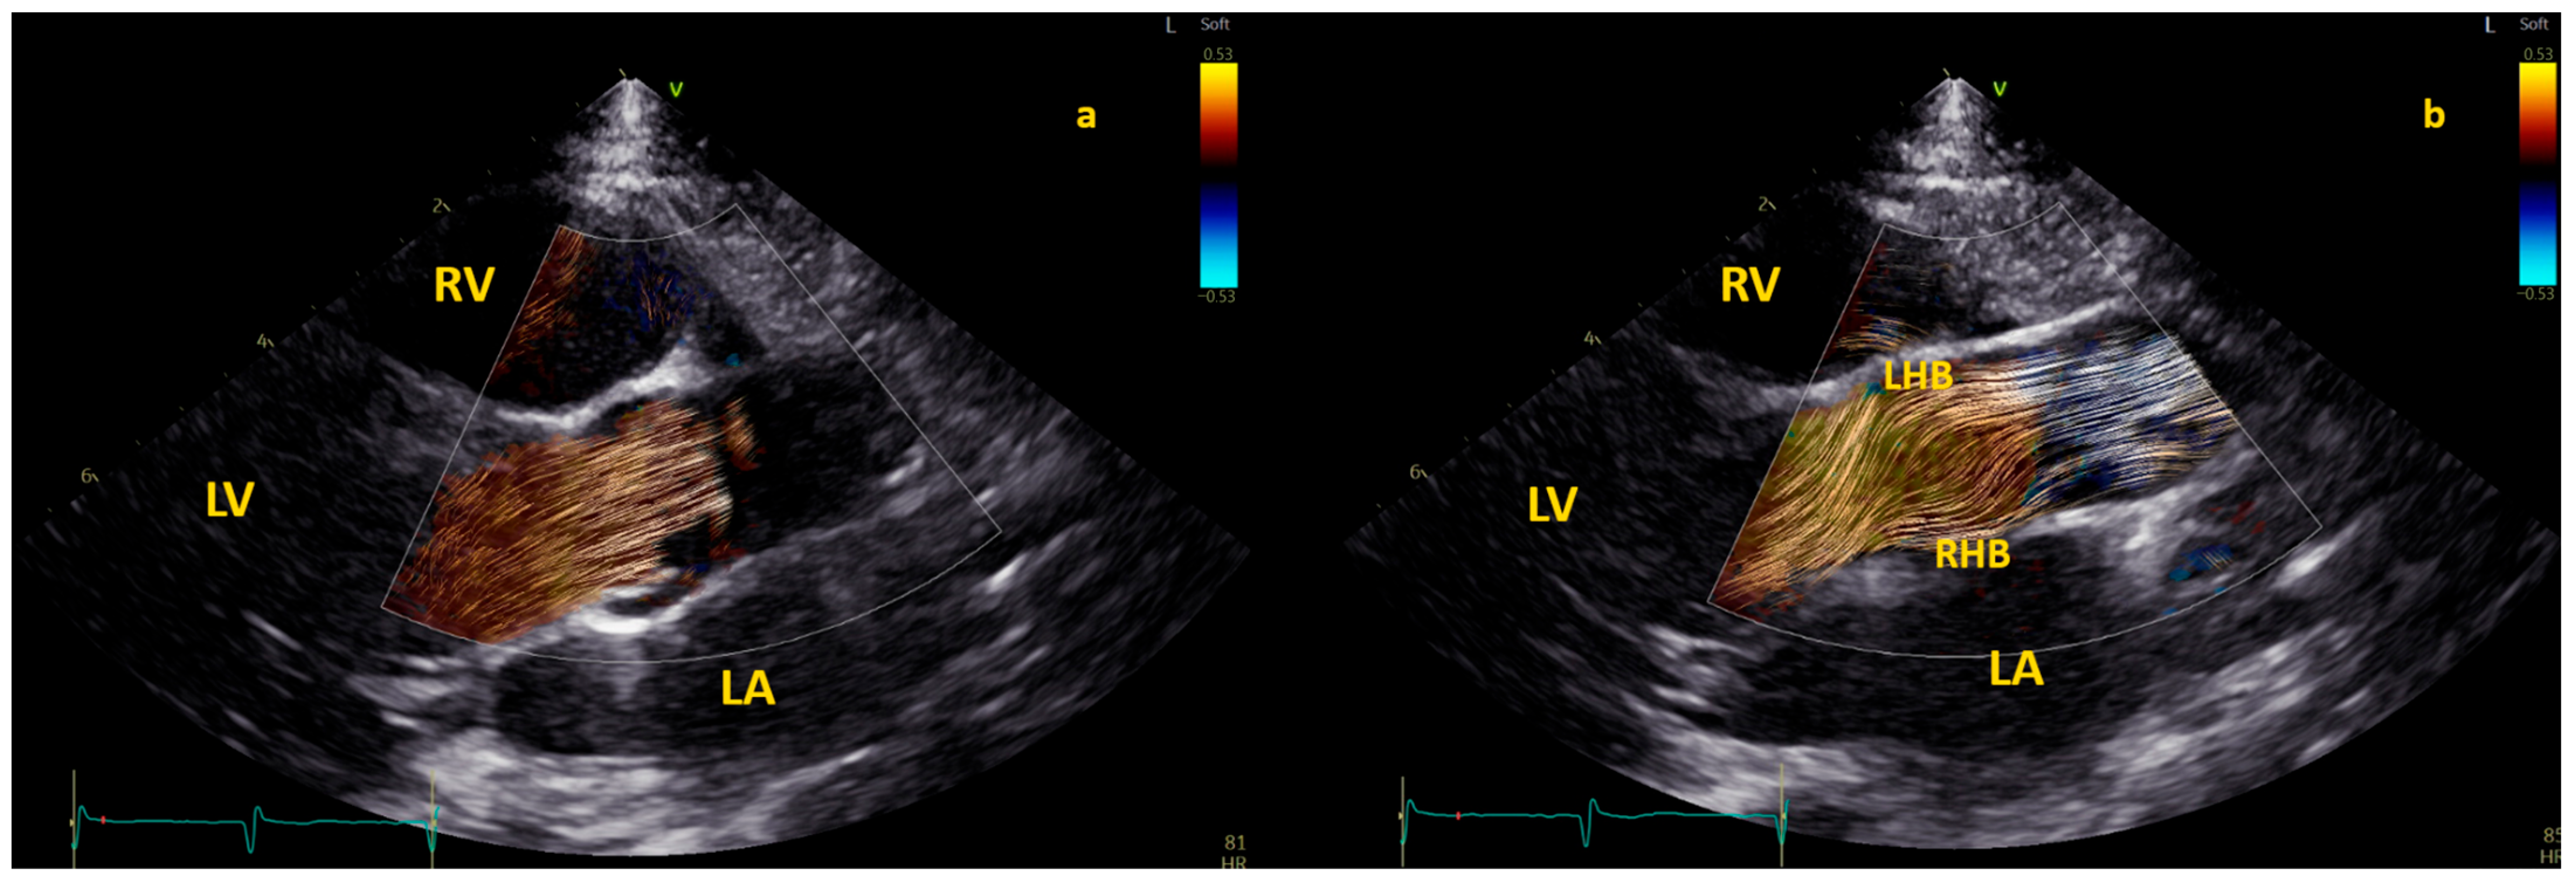

Application of BST echocardiography for the evaluation of aortic flow in children is still limited but promising [8]. In 100 healthy children [19], specific patterns of aortic flow by BST were observed. Initially, in early systole, the flow in the aortic root is laminar; however, in mid-systole, the flow splits into two helical branches going in opposite directions (one to the right ascending aortic wall and the other toward the left aortic wall) and vortices form close to the sino-tubular junction [19]. Finally, the flow returns laminar during late systole [19]. This pattern is described in Figure 4.

Figure 4. The three different phases of aortic flow in a healthy child. The first phase is shown in the left picture (a), where the blood flow is laminar in the aortic root. Both second and third phases are shown in the picture on the right (b): double helical flow (with a right–handed branch (RHB) to the left aortic wall, and a left–handed branch (LHN) to the right aortic wall) and laminar in ascending aorta. BST was performed from a focused and zoomed view of the aortic root and the ascending aorta. The color Doppler sector with BST was positioned over the aortic root in the parasternal long-axis view and the ascending aorta in the suprasternal view. Acquisitions included at least 2 cardiac cycles at a range of 380 to 560 frames per second with Nyquist limits ranging from 53 to 58 cm/s.